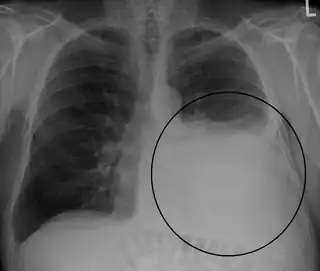

![]() Radiografía de tórax que muestra un derrame pleural en el pulmón izquierdo (señalado con un círculo) | ||

El derrame se hace visible en la radiografía cuando es mayor de 75 ml, puede aparecer libre o loculado. En caso de que existan dudas, es recomendable la realización de una radiografía en decúbito lateral del lado afecto. El derrame pleural puede presentar imágenes radiológicas atípicas como:

- La imagen de la radiografía de tórax en el derrame pleural es usualmente característica a 200 ml de líquido pleural (LP) producen borramiento de los ángulos cardiofrénico y costodiafragmático. 50 a 75 ml de LP producen borramiento del ángulo costodiafragmático posterior en la radiografía lateral, observándose el denominado “signo del menisco”. La sensibilidad de la radiografía de tórax para detectar DP es 24-100% con especificidad 85-100% y la sensibilidad para detección del DP por utrasonido es 93% con especificidad 96%.